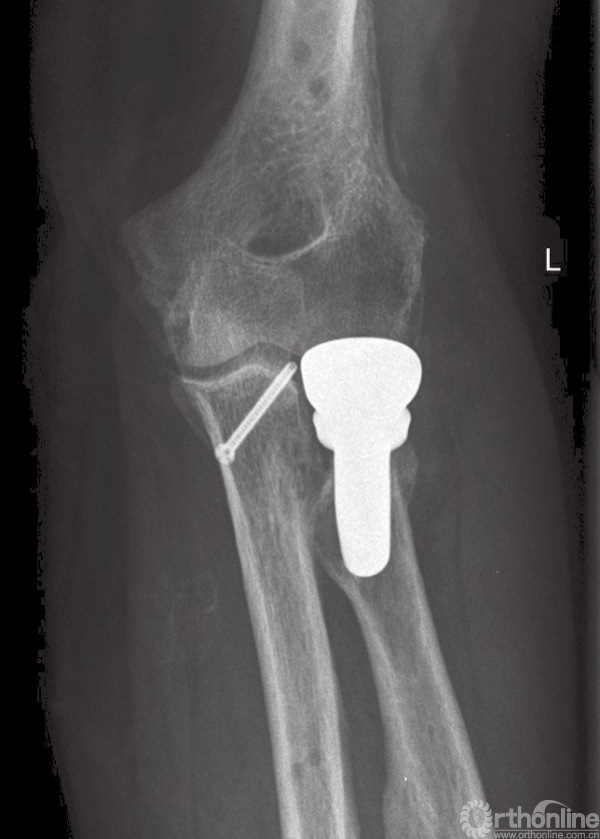

图8 (与图2为同一患者)使用铰链式外固定支具后的术后正位X线片

如果伸肌总腱止点损伤应进行修复,Kocher's间隙的筋膜也应修补(图9和图10)。如果在修复桡骨头及外侧副韧带后,肘关节屈曲40°以上仍发生半脱位,则还需经内侧入路,以同样方法修复内侧韧带复合体(图11)。

图9 (与图2为同一患者)使用铰链式外固定支架后的术后侧位X线片

图10 长期随访患者,正位片显示桡骨头假体位置满意,伴有少量异位骨化